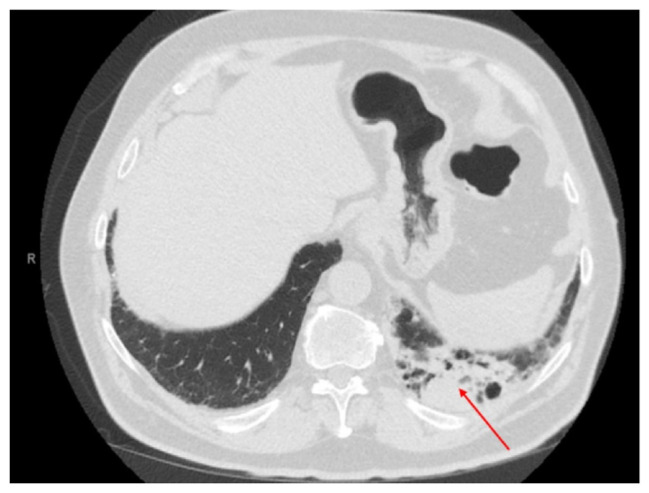

如今,检查点抑制剂在不同类型癌症的治疗中发挥着重要作用。然而,我们已经看到了免疫治疗相关不良事件的变体,通常从疲劳到神经病变到严重的破坏性并发症,如重症肌无力(MG)引起的呼吸衰竭,就像我们在本病例中看到的那样。我们的患者开始使用派姆单抗,在开始治疗三周后出现MG引起的严重呼吸衰竭。此外,患者出现肌炎、轻度心肌炎和肝炎,均与派姆单抗有关。

Nowadays, checkpoint inhibitors play a major role in the management of different types of cancers. However, we have seen variants of immune therapy-related adverse events, which usually are variables from fatigue, to neuropathy to severe devastating complications such as respiratory failure due to myasthenia gravis (MG), as we saw in our case. Our patient was started on pembrolizumab, and they developed severe respiratory failure attributed to MG after three weeks from treatment initiation. Also, the patient presented with myositis, mild myocarditis and hepatitis, which were all related to pembrolizumab.